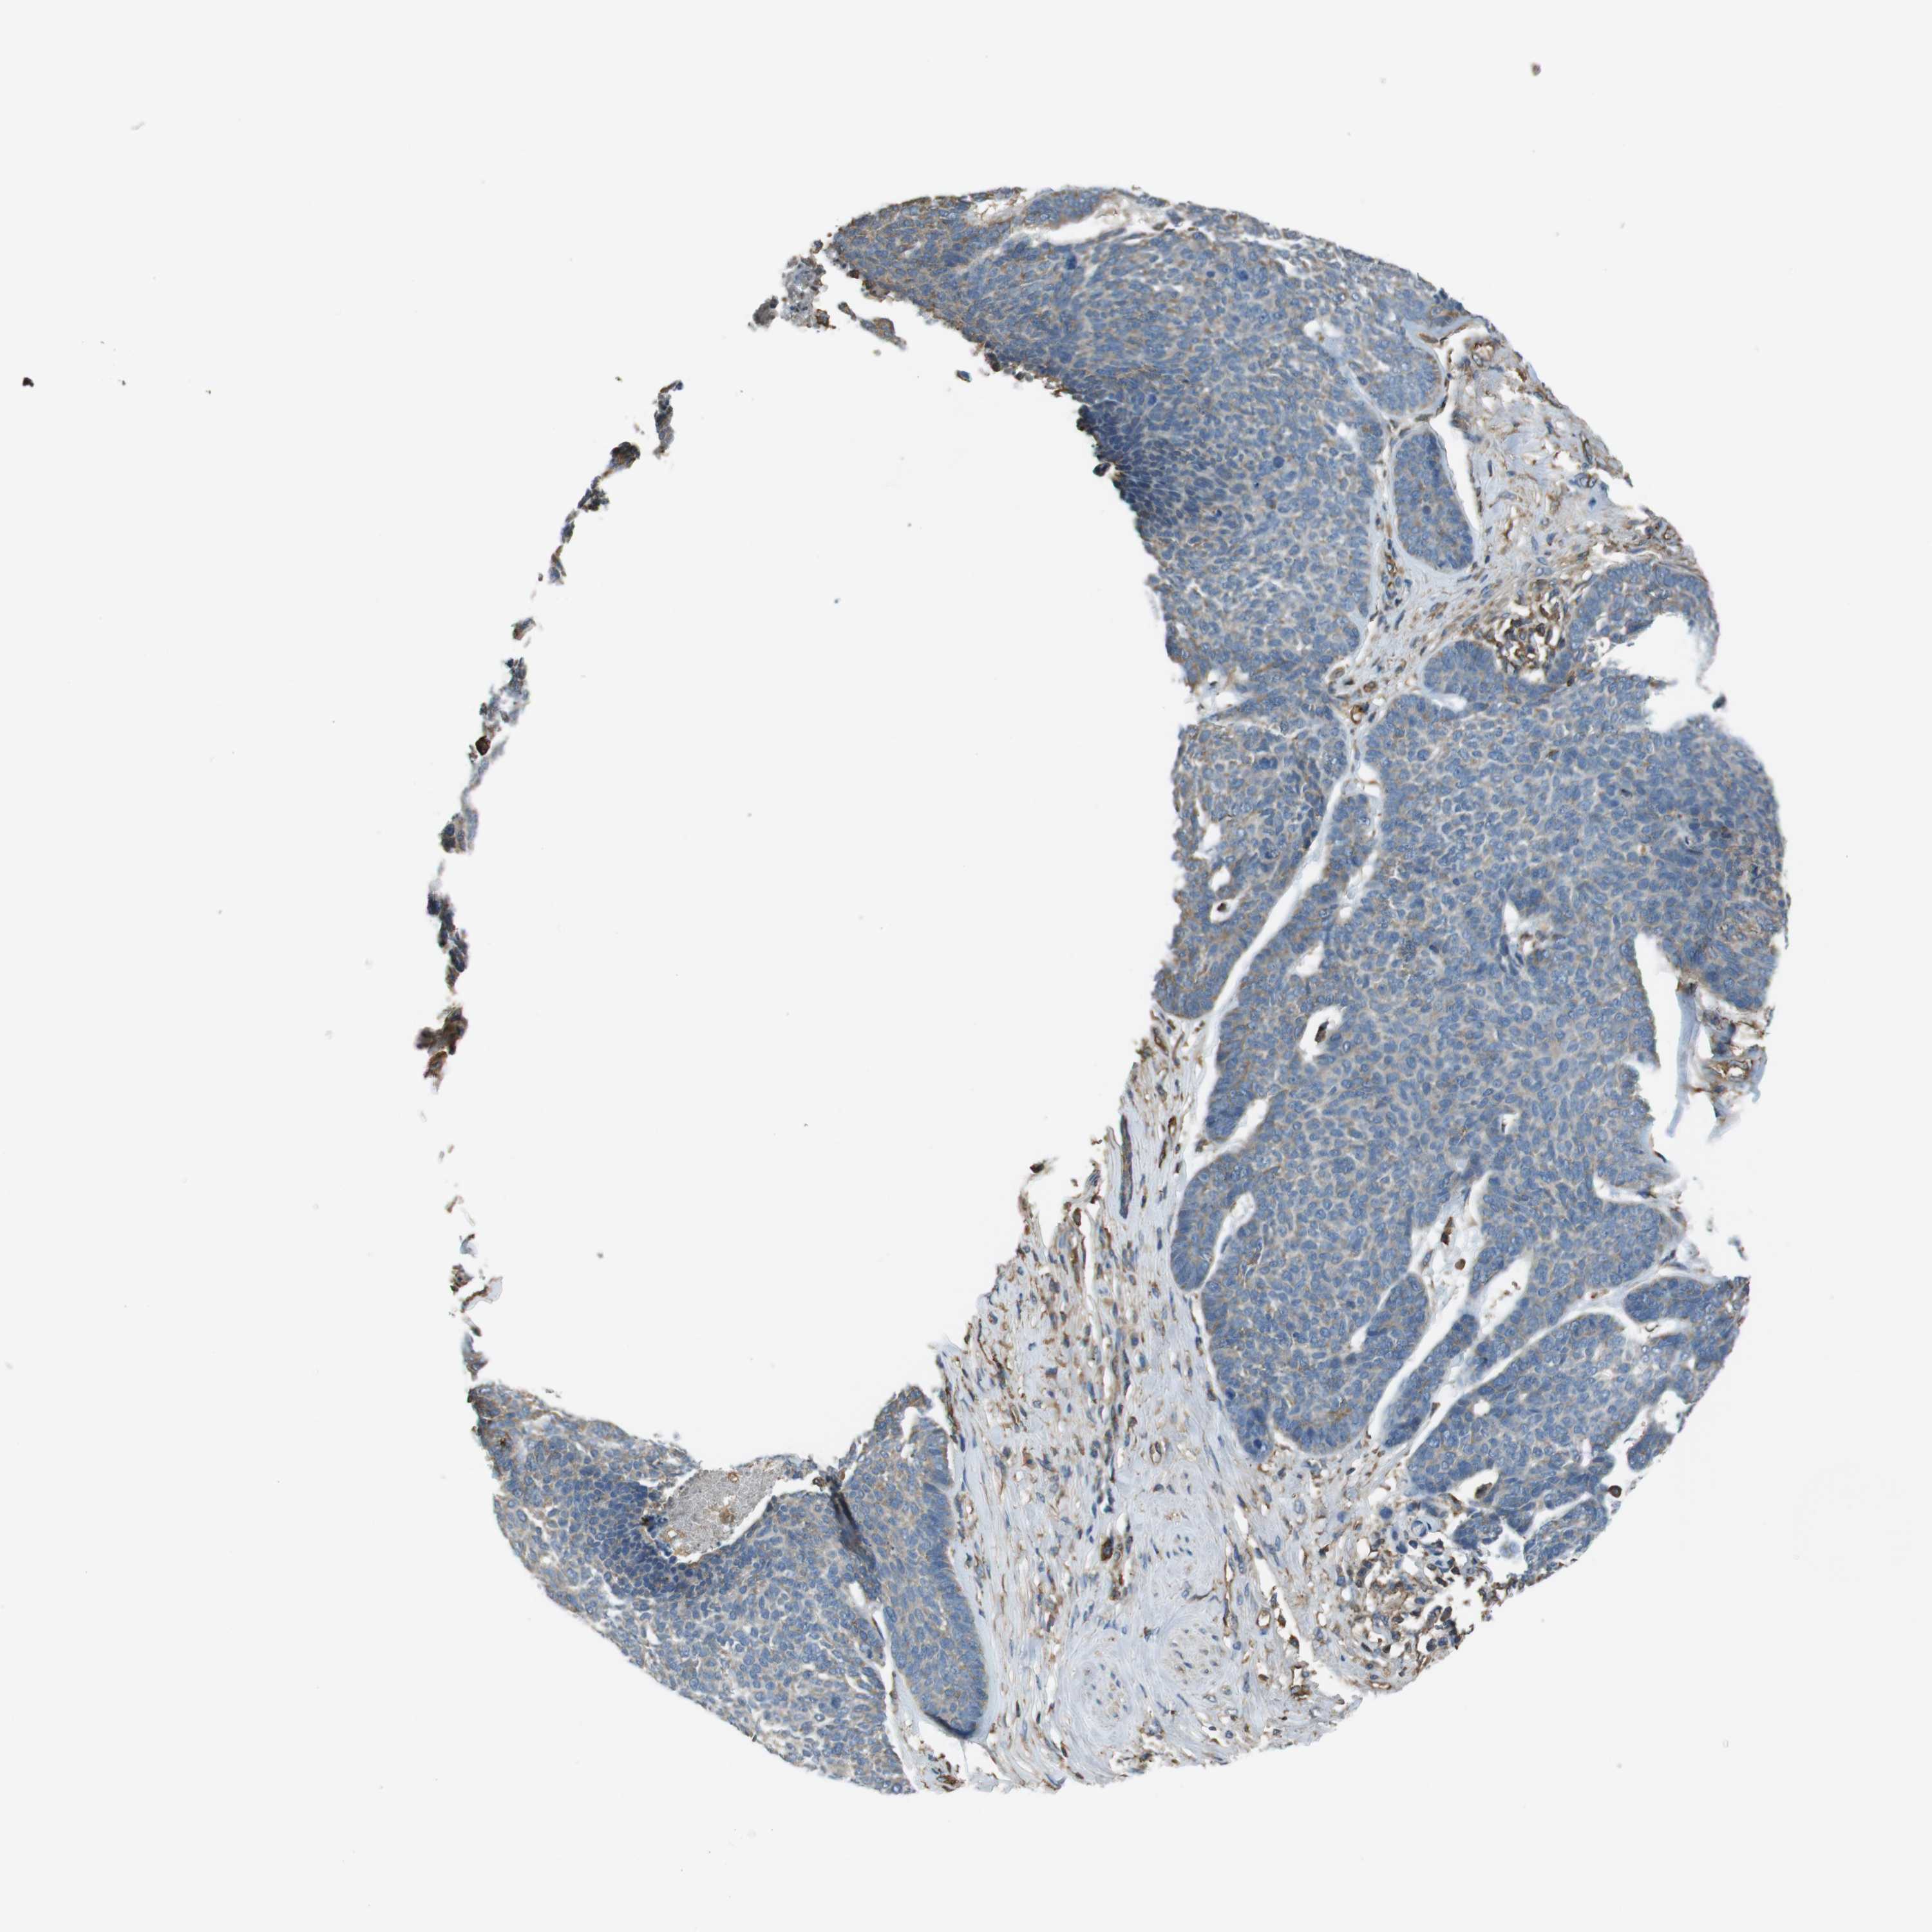

SKIN CANCER - Protein expressioni

A mouse-over function shows sample information and annotation data. Click on an image to view it in a full screen mode. Samples can be filtered based on level of antibody staining by selecting one or several of the following categories: high, medium, low and not detected. The assay and annotation is described here.

Antibody stainingi

Antibody staining in the annotated cell types in the current human tissue is reported as not detected, low, medium, or high, based on conventional immunohistochemistry profiling in selected tissues. This score is based on the combination of the staining intensity and fraction of stained cells.

Each image is clickable and will lead to virtual microscopy that enables deeper exploration of all samples and also displays staining intensity scores, fraction scores and subcellular localization as well as patient and tissue information for each sample.

Antibody HPA014050

Staining

High

Medium

Low

Not detected

Intensity

Strong

Moderate

Weak

Negative

Quantity

>75%

75%-25%

<25%

None

Location

Nuclear

Cytoplasmic/membranous

Cytoplasmic/membranous,nuclear

Squamous cell carcinoma, NOS

Basal cell carcinoma

Adnexal tumor, benign